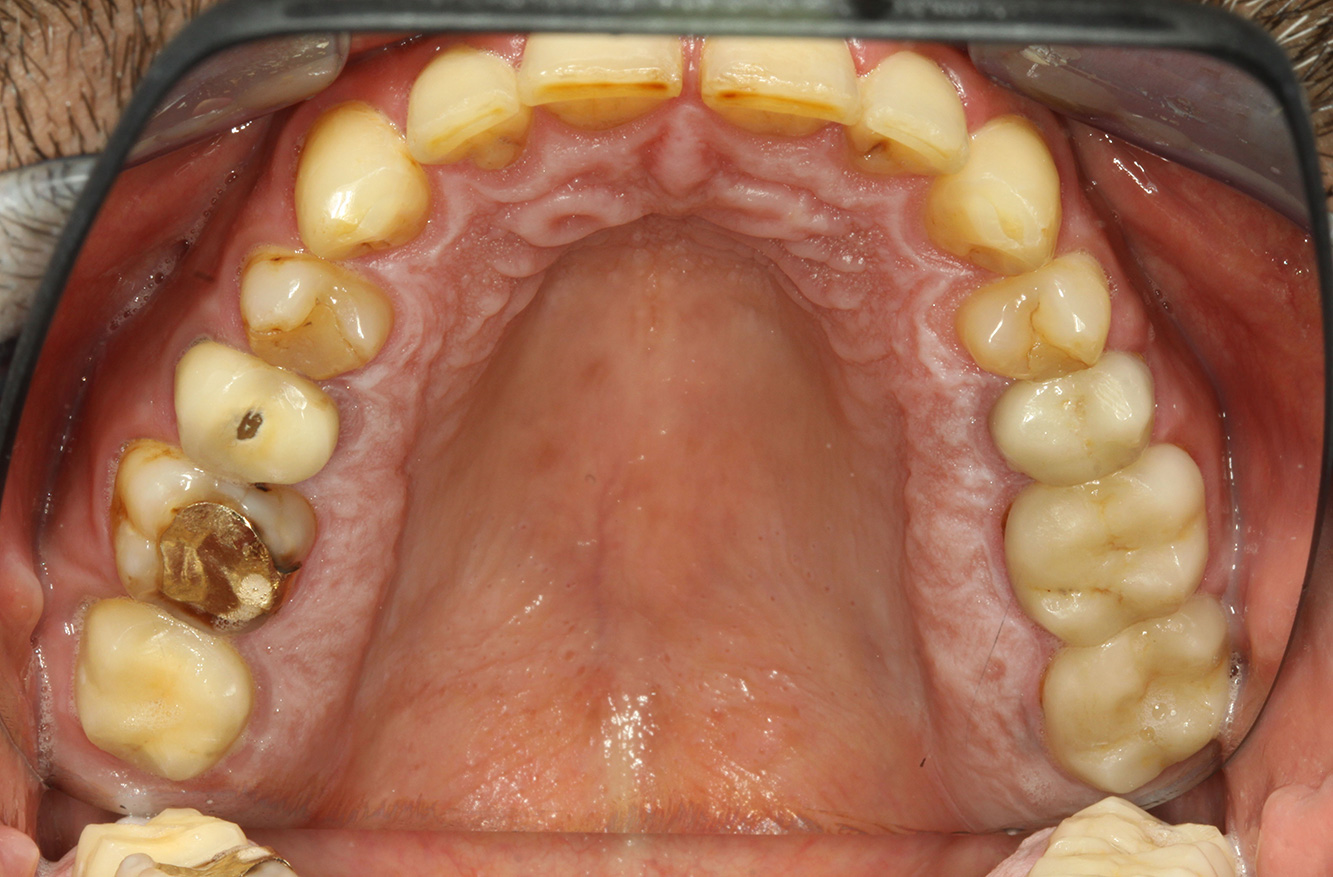

Il paziente ha 39 anni e in passato è stato sottoposto ad un intervento per la sostituzione della valvola aortica dovuta a insufficienza valvolare ed endocardite. Assume regolarmente l'ASS 100 come anticoagulante. Per quel che riguarda lo stile di vita, il regime alimentare seguito dal paziente è classificato come “dieta che favorisce la formazione della carie”, per via del consumo regolare di cibi ad alto contenuto di zuccheri e dei sei-sette pasti consumati al giorno. La salute orale del paziente indica un rischio moderato di carie, con lesioni attive. Il rischio di parodontite è basso, tuttavia il paziente è affetto da gengivite. Si formulano quindi i seguenti consigli per il trattamento di profilassi.

Per la seduta di profilassi non si possono formulare consigli per strumenti specifici. Si può ricorrere a un'applicazione mirata di air-polishing e lucidatura con testina rotante per rimuovere delicatamente placca e discromie lungo i margini del restauro e per ridurre le nicchie dove i batteri cariogeni possono formare nuove colonie (19).

Si consiglia una fluorizzazione per stimolare ulteriormente la prevenzione della carie, prevenire in particolar modo nuove formazioni intorno ai margini del restauro e per sigillare le superfici radicolari. Entrambi i provvedimenti possono ridurre la sensibilità dei denti alla temperatura.